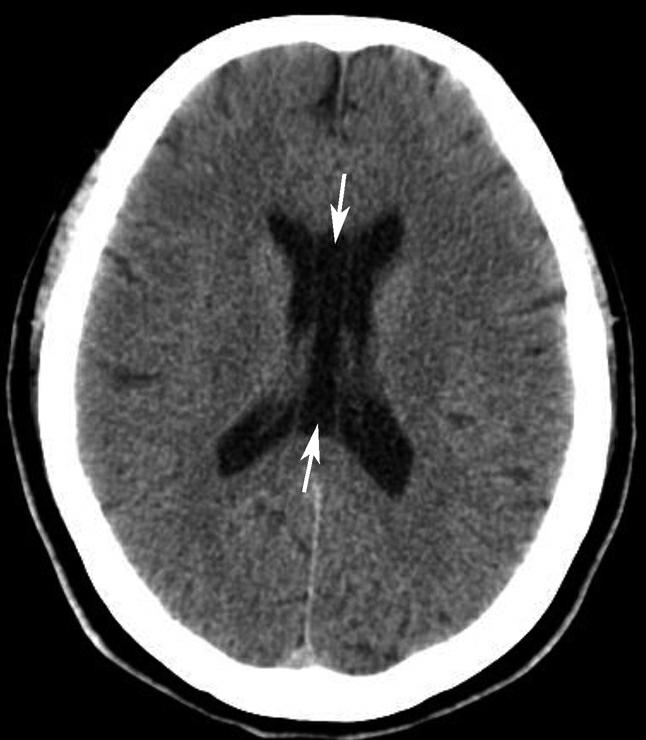

第三脑室正常成人前后径约12mm,左右宽约5mm,上下径也约为12mm。侧脑室后角两侧有时大小不等,右侧后角上下径约为38mm,左右径约为20mm;左侧后角上下径约为28mm,左右径约为15mm。测量双侧侧脑室前角间径与同平面脑横径的比值(R),正常平均值为30%。轻度扩大时为31%~39%,中度扩大为40%~46%,重度扩大时>47%。脑积水或脑萎缩等病理情况下脑室系统会扩大。不同年龄组正常脑室系统测量值存在差异,整体表现出测量值随着年龄增大而增大的趋势(图1-2-83、图1-2-84)。

图1-2-84 侧脑室测量

R=双侧侧脑室前角间径(a)/同平面脑横径(b)